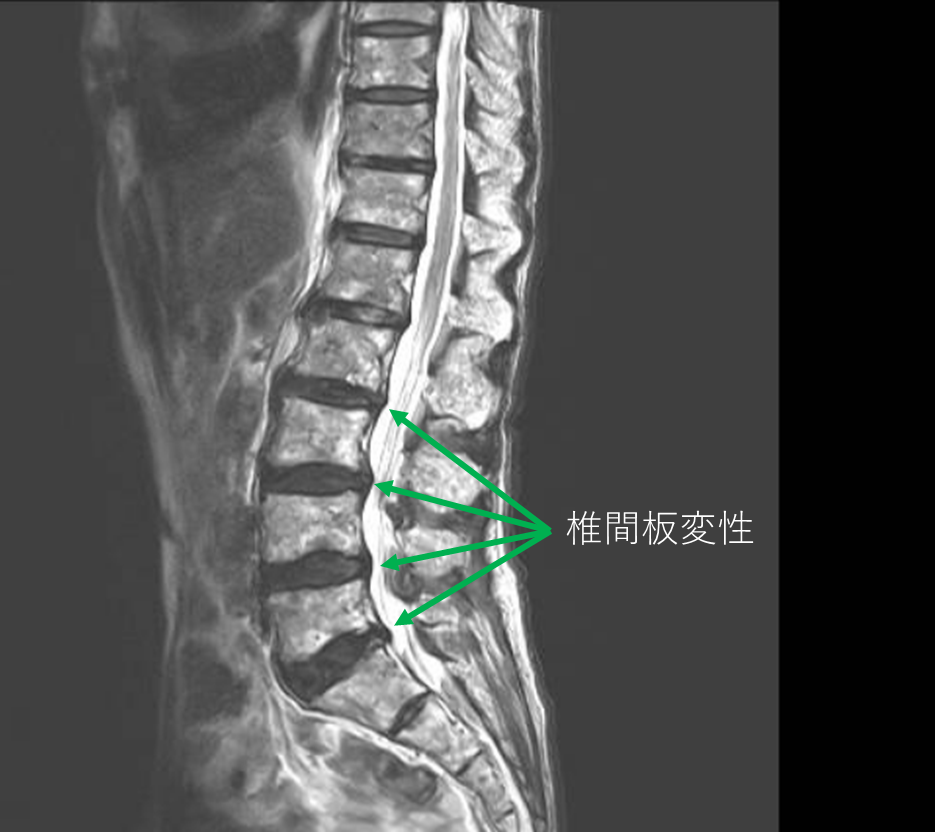

- L1/2,2/3,3/4,4/5,5/s-椎間板変性

以上の事が画像上認められます。

・L2/3,3/4,4/5,5/s-椎間板変性による椎間孔狭窄を認め、主症状の原因と考えられる。